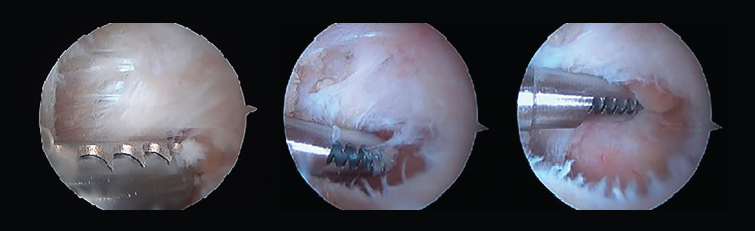

Figura 8. A: en una primera opción, se realiza la resección ósea mediante un osteotomo de 5 mm; B y C: la segunda opción es realizar la resección mediante el uso de una fresa artroscópica.

Tras la disección completa del PPA y la evaluación y el tratamiento de la patología asociada del FHL, si es necesario, podemos iniciar el procedimiento de resección ósea(11,12,13). Así, en caso de pinzamiento óseo, los procedimientos se realizan de acuerdo con la etiología de este (Figuras 8 A, B y C).